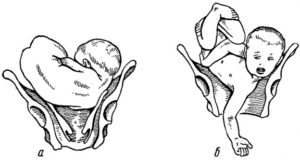

Тазовое предлежание может быть ягодичным, ножным, смешанным, коленным – каждое из них врач легко диагностирует при обычном осмотре, после чего необходимо будет подтверждение УЗИ. Тазовое предлежание считается не совсем нормальным положением и для малыша, и для мамы – хоть прямых больших угроз и не несет.

Также признаки тазового предлежания плода выявляют себя в ходе влагалищного исследования. К примеру, при ягодичном предлежании прощупывается мягкая объемная часть, паховый сгиб, копчик и крестец.

При смежном ягодичном и ножном предлежании можно определить стопы малыша с пяточным бугорком и короткими пальцами (отличными от пальцев на руках), расположенными на одной линии.

Такие признаки выявляются во время влагалищного исследования. Например, при ягодичном положении врач прощупывает паховый сгиб, мягкую объемную часть, крестец и копчик. При смешанном ножном и ягодичном расположении определяются стопы ребенка с пяточным бугорком и пальцами, которые расположены на одной линии. Чтобы уточнить диагноз обязательно проводят УЗИ.

Во-вторых, при родах головка малыша может запрокинуться, и она с трудом выходит наружу. Велик риск нанесения ребенку травмы.

В-четвертых, в процессе родов возможно запрокидывание ручек, что может привести к травмам.